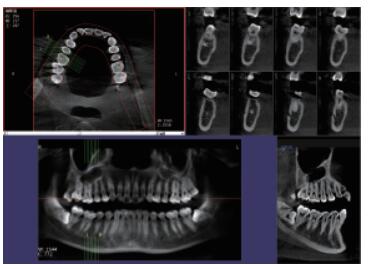

4、口腔CBCT(口腔CT)

CT相對其他牙片來講,不管是功能還是設備上都是比較高級的,醫生可在電腦上進行模擬種植360°的旋轉查看口腔狀況,不遺漏任何一個角落,主要用于根管治療前、阻生牙、根尖囊腫、種植牙、正畸等。